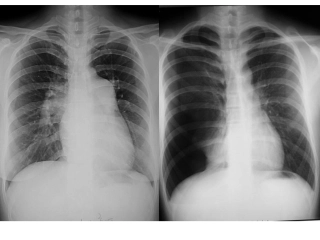

肺结核影像学纵君虐我千百遍,我却待君如初恋——TB有感肺结核的CT特点:三多三少•多灶性、多态性、多钙化性•少肿块性、少结节堆聚性、少...